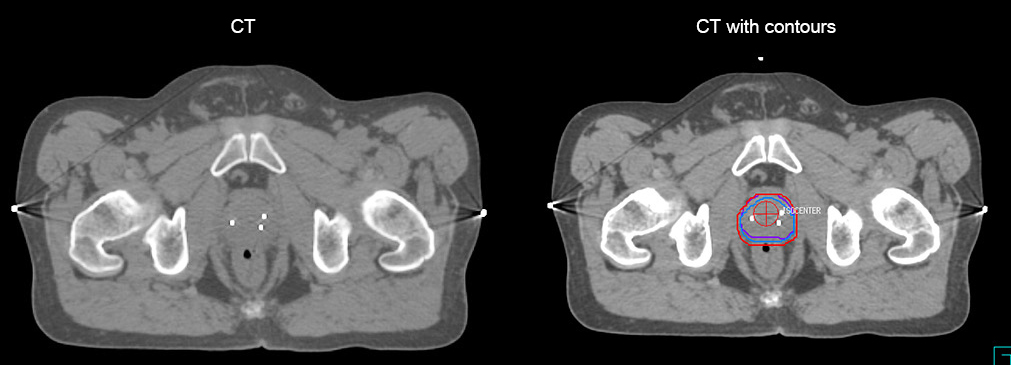

“The biggest problem for CT-based planning, especially in prostate, is you can’t see the cancer very well,” says Dr. Stevens. “On CT it can be quite challenging to see the edge of the prostate especially at the apex. When the edge of the prostate can’t be delineated well on CT, radiation oncologists will increase their margins a little bit so they don’t miss it, but that can also increase toxicity.”

“Using MR, the prostate is well delineated. We quickly see the edges of cancerous tumors like in prostate cancer, and as normal structures can be defined, we can optimize the treatment plan to protect these organs and their normal function. This can potentially improve the outcome. And it improves workflow as well. We can contour more quickly, confident that the tumor is going to be in the field.”

“There are some general challenges in RT imaging – even with CT – such as imaging geometry and positioning accuracy. Positioning is extremely important in RT, because we need reproducibility between imaging and treatment position. We also need accurate geometry so we can be sure our treatment plan is properly delivered during the treatment,” says Dr Yan.

“The Ingenia MR-RT configuration includes an external laser positioning system for patient alignment and a flat tabletop for imaging the patient in treatment position. Ingenia MR-RT also came with a special QA package for regular monitoring of precision. Our Ingenia 3.0T scanner achieves good geometric accuracy – within a millimeter for most patients – and the phantom measurement is even better,” he adds.